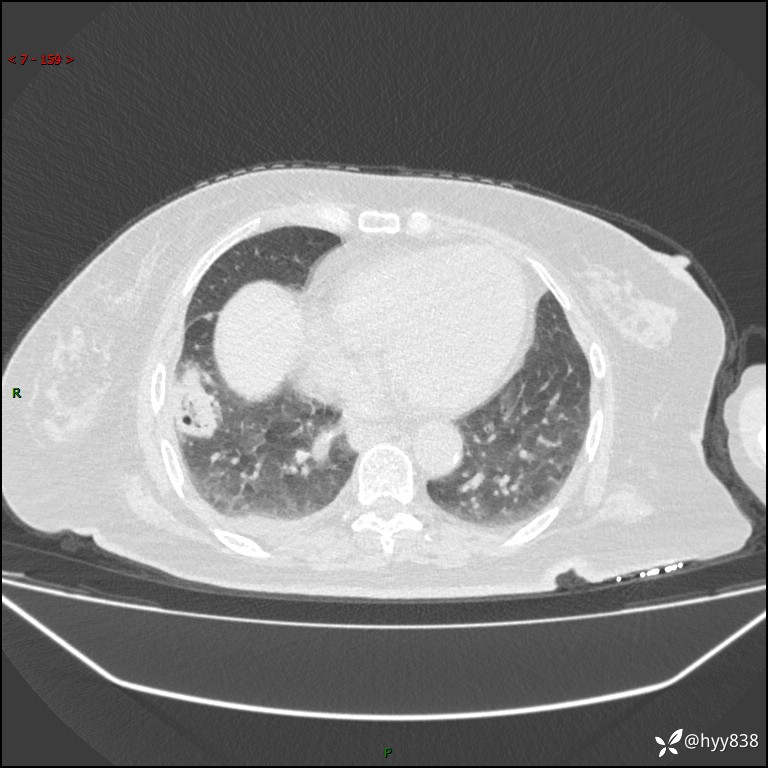

患者性别:女

患者年龄:57岁

简要病史:昏迷入院

胸部 CT平扫、